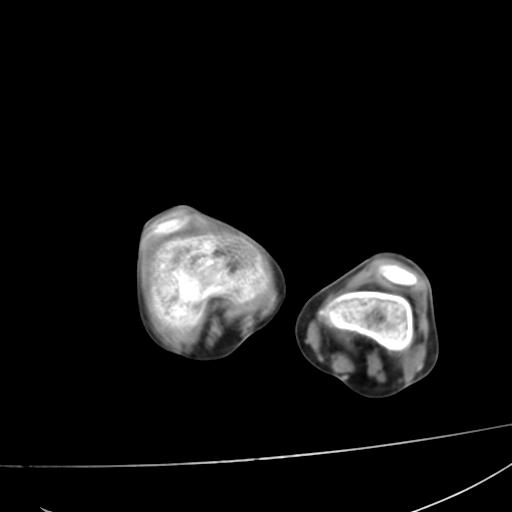

标题: PED0940:M12Y,左股骨下端酸痛畸形 [打印本页]

标题: PED0940:M12Y,左股骨下端酸痛畸形

12岁男孩,左膝关节肿痛8年,近月明显

内生骨软骨瘤?

血友性关节病?